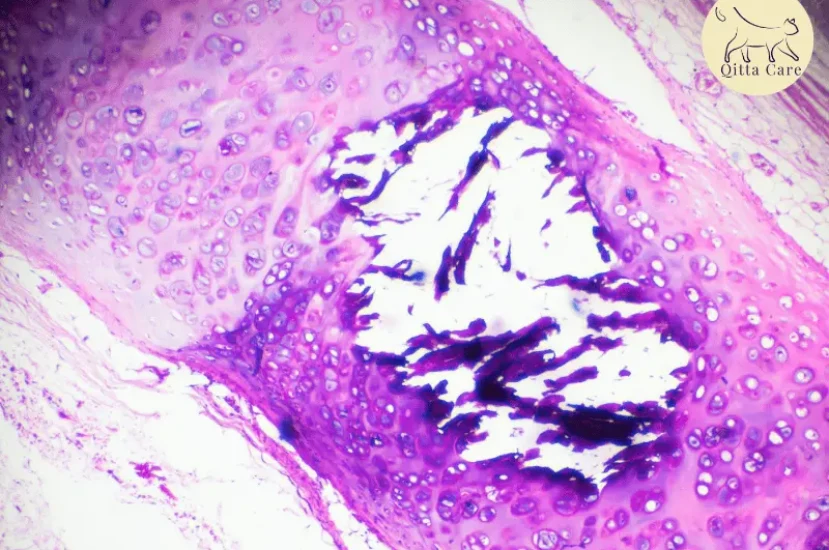

- التهاب الرئة الدهني الذاتي: نوع من التهاب الرئة البيني يتميز بوجود خلايا بلعمية تحتوي على دهون ناتجة عن انهيار أنسجة الرئة والدم، يؤثر بشكل شائع على القطط القديمة.

- تليف الرئة البيني وهيحالة توجد فيها خلايا بلعمية في الحويصلات الهوائية.

- التهاب الرئة الدهني الذاتي شائع في القطط المصابة بالتهاب القصبات الهوائية وتمدد القصبات الهوائية المزمن.

- تليف الرئة البيني يحدث غالبًا نتيجة لتحفيز المناعة أو ترسب مركبات المناعة.